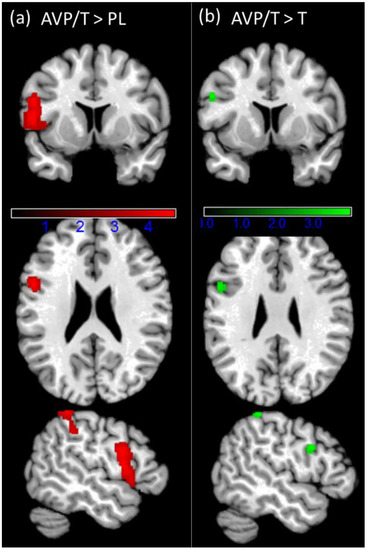

| Contrast | Region | k | T | x | y | z |

|---|---|---|---|---|---|---|

| L Inferior Occipital Gyrus | 10,572 | 9.84 | −34 | −90 | −12 | |

| L Lingual Gyrus | 9.28 | −22 | −100 | −14 | ||

| R Inferior Occipital Gyrus | 9.11 | 28 | −96 | −6 | ||

| L Middle Occipital Gyrus | 8.26 | −34 | −94 | 0 | ||

| L Inferior Occipital Gyrus | 8.06 | −48 | −68 | −16 | ||

| R Middle Occipital Gyrus | 7.89 | 28 | −90 | 6 | ||

| Loss > win | L Calcarine Gyrus | 1514 | 4.74 | −22 | −66 | 4 |

| R Calcarine Gyrus | 4.63 | 4 | −72 | 16 | ||

| R Lingual Gyrus | 4.29 | 10 | −64 | 2 | ||

| L Cuneus | 3.70 | −10 | −80 | 16 | ||

| R Angular Gyrus | 4.91 | 34 | −70 | 46 | ||

| R Middle Occipital Gyrus | 4.69 | 38 | −66 | 34 | ||

| L Inferior Parietal Lobule | 573 | 5.20 | −34 | −60 | 50 | |

| L Angular Gyrus | 3.33 | −44 | −54 | 32 | ||

| R Inferior Temporal Gyrus | 380 | 5.46 | 50 | −4 | −36 | |

| R Medial Temporal Pole | 4.76 | 48 | 16 | −28 | ||

| R Temporal Pole | 4.70 | 50 | 16 | −24 | ||

| L Paracentral Lobule | 331 | 4.69 | −2 | −36 | 80 | |

| L Precuneus | 4.44 | −4 | −40 | 80 | ||

| L IFG (p. Triangularis) | 274 | 4.13 | −46 | 14 | 28 | |

| L Middle Frontal Gyrus | 3.46 | −46 | 20 | 36 | ||

| R Superior Medial Gyrus | 272 | 5.17 | 14 | 60 | 32 | |

| L Precentral Gyrus | 12,344 | 10.05 | −38 | −12 | 50 | |

| L Posterior−Medial Frontal | 8.27 | −4 | −10 | 64 | ||

| R Posterior−Medial Frontal | 8.14 | 8 | −6 | 66 | ||

| L MCC | 7.54 | −14 | −26 | 44 | ||

| R Middle Frontal Gyrus | 7.31 | 42 | −4 | 52 | ||

| Win > loss | R Precentral Gyrus | 7.08 | 52 | 0 | 48 | |

| L MCC | 6.86 | −6 | 4 | 38 | ||

| L Insula Lobe | 835 | 5.97 | −44 | 6 | 6 | |

| L Rolandic Operculum | 5.76 | −50 | 4 | 4 | ||

| L IFG (p. Triangularis) | 4.51 | −36 | 22 | 8 | ||

| R IFG (p. Opercularis) | 726 | 5.55 | 38 | 12 | 12 | |

| R Insula Lobe | 4.85 | 32 | 26 | 4 | ||

| R Rolandic Operculum | 3.24 | 58 | 0 | 12 | ||

| R Superior Temporal Gyrus | 497 | 5.21 | 50 | −38 | 22 | |

| R Rolandic Operculum | 3.61 | 40 | −30 | 20 | ||

| R Middle Temporal Gyrus | 299 | 6.37 | 42 | −68 | 8 |